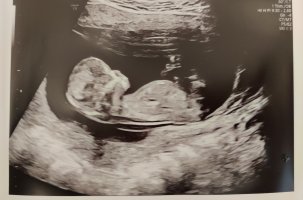

Jente!Alt bra med lille Jordmor mente 60 % sjans for jente Hva tror dere?? 13+0

JenteAlt bra med lilleJordmor mente 60 % sjans for jente

Hva tror dere?? 13+0